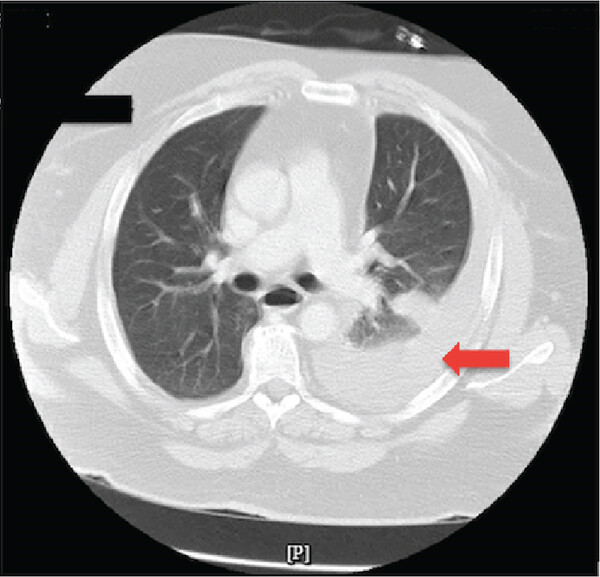

У пациента были взяты посевы крови и мокроты, определен уровень прокальцитонина и проведены лабораторные тесты для выявления возбудителя пневмонии. В связи с подозрением на вторичную бактериальную инфекцию эмпирически назначен цефтриаксон, а для купирования боли – морфин. Пациент был госпитализирован для дальнейшего обследования и лечения. Результаты бакпосевов были отрицательными, но удалось обнаружить частицы аденовируса и риновируса. Из-за подозрения на сопутствующий астматический бронхит, пациенту были назначены метилпреднизолон, ипратропиум-альбутерол и ингаляции будесонида. На пятый день пребывания в клинике усилились симптомы дыхательной недостаточности и боль в левой части грудной клетки. Повторная КТ выявила выраженный левосторонний гемоторакс (рис. 2).

Рисунок 2. КТ-снимок грудной клетки в аксиальной проекции (на 5-й день госпитализации) показывает большое скопление жидкости слева (красная стрелка), без ушибов.